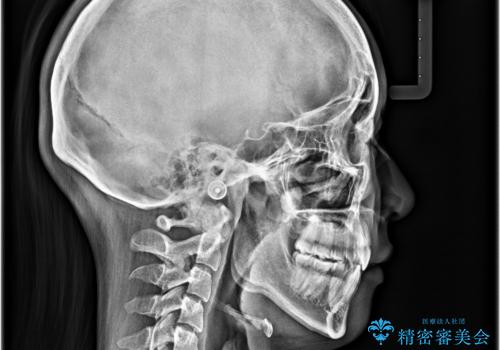

- 口元の突出感と口の閉じにくさを気にして来院された患者様です。

上下左右第一小臼歯4本を抜歯し、ワイヤー装置にて口元を引っ込めるよう矯正治療を行うこととしました。

口元の突出感が改善されてことで、下唇に引っかかっていた上顎前歯も気にならなくなりました。